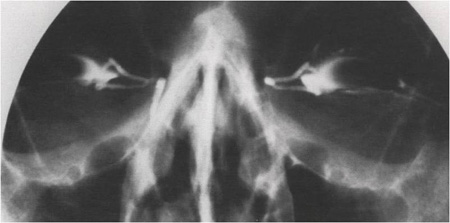

´«¹°±æÀÇ ¸·Èù ºÎÀ§¿Í Á¤µµ¸¦ ÆÄ¾ÇÇÒ ¼ö ÀÖ´Â ¹æ»ç¼± »çÁø

´«¹°±æ ¸·Èû (ºñ·ç°ü Æó¼â)ÀÇ °Ë»ç

* ÁÖ»ç±â¸¦ ÀÌ¿ëÇÏ¿© ´«¹°ÀÌ ÄÚ·Î Èê·¯³ª°¡´ÂÁö¸¦ °Ë»ç

* ¹æ»ç¼± »çÁøÀ» ÀÌ¿ëÇÏ¿© ´«¹°±æÀÇ ¸·Èù ºÎÀ§ ¹× Á¤µµ¸¦ Á¤È®È÷ ÆÄ¾ÇÇÔ